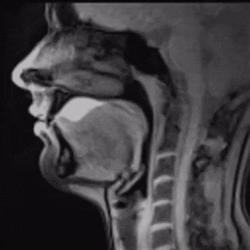

正在分泌的唾液不只是覆盖面包,避免它沾在我的嘴上,还提取了面包的味道。我先尝到了甜味,这是因为我的唾液溶解了面包中的糖分,并将它们送到了识别甜味的味蕾中。随后,面包的咸味与香味也开始显现出来。

味蕾需要一种液体介质来传递香味分子,这正是唾液进化的目的。面包本身不含汁液,所以你需要靠唾液享受美味,事实上,你还得靠唾液将它吃下去。

唾液中的一些酶可以预先消化食物,所以你的味蕾,当然还有鼻腔中的受体,都可以在你吞咽前分析嘴里的东西。

淀粉酶是其中最重要的一种,它将淀粉分解并转化为单糖,所以你咀嚼的时间越长,面包的味道越甜。

而对于人类来说,唾液的一个主要作用是让食物变得润湿,食物就可以滑动或流动,而你就能吞下它们。如果没有了唾液,事情肯定会变得十分棘手,这在吃饼干大赛中得到了完美的验证。